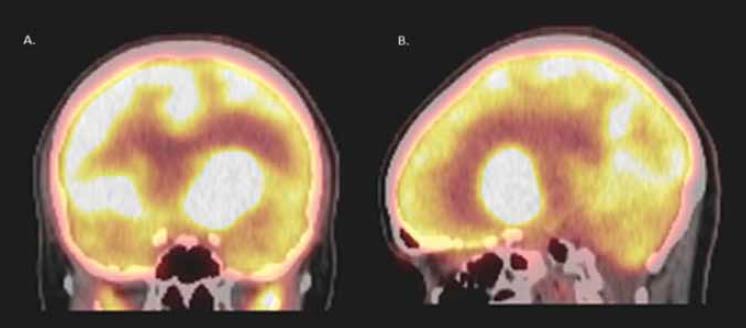

Posteriormente en el seguimiento se decidió realización de PET/CT con 18-FDG, evidenciando nueva masa intraaxial intensamente hipermetabólica (SUV= 47,7) localizada en la sustancia blanca fronto-temporal izquierda que comprometía región núcleo-basal y que producía efecto de masa, edema vasogénico y ventriculomegalia contralateral (figura 1). Se realizó una segunda biopsia guiada por neuronavegación y abordaje transventricular, con reporte histopatológico de linfoma B difuso de célula grande (alto grado) primario del sistema nervioso central (LPSNC) CD20 (+) (figura 2), se dio quimioterapia con metotrexate, citarabina y carmustina (protocolo BAM), adicionalmente se realizó consolidación con trasplante autólogo de médula ósea. Presentó recaída tumoral al día

(A) Corte coronal. (B). Corte sagital. Se observa una masa intraaxial intensamente hipermetabólica (SUV: 47.7) localizada en la sustancia blanca fronto-temporal izquierda que compromete la región núcleo-basal y que produce efecto de masa, edema vasogénico y ventriculomegalia contralateral. |

| Figura 1. PET/CT (tomografía con emisión de positrones con radiofármaco f-18 FDG |

Con respecto a los estudios adicionales realizados en nuestra paciente para determinar la etiología definitiva que explicase el compromiso endocrinológico a nivel hipotalámico e hipofisiario, la tomografía con emisión de positrones con radiofármaco F-18 FDG (PET/CT) fue la herramienta que permitió en última instancia la identificación y localización de la lesión blanco para realizar la segunda biopsia que confirmó el diagnóstico de LPSNC. La importancia de dicho estudio radica en la capacidad que posee para identificar un compromiso sistémico en pacientes con enfermedad neoplásica hematológica confirmada(10). En nuestro caso se puede observar una evolución desafortunada y poco favorable que podría estar en relación con la alta actividad proliferativa tumoral expresada en la tomografía con F-18 FDG.